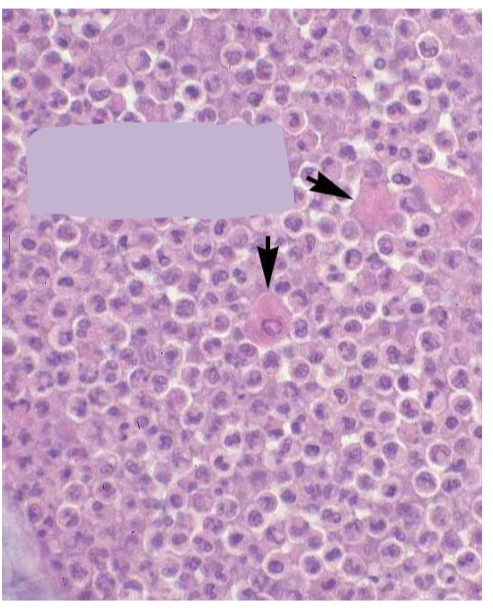

What are the arrow heads pointing to?

acantholytic keratinocytes

What is the arrow head pointing to?

acantholytic keratinocyte